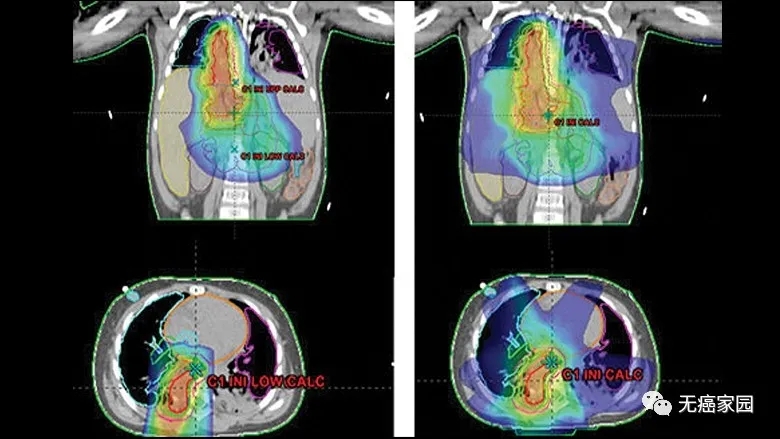

与X线调强放疗(IMXT)相比,笔形束扫描(PBS)质子治疗具有更优的剂量适形性及靶区覆盖情况。

使用质子(左)与X射线治疗(右) 质子治疗对周围重要器官损伤更少